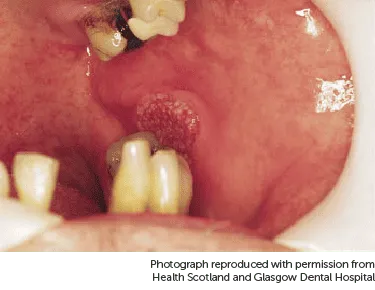

Hãy thử so sánh biểu hiện của bạn với những hình ảnh ung thư khoang miệng sau đây:

Mảng đỏ ung thư